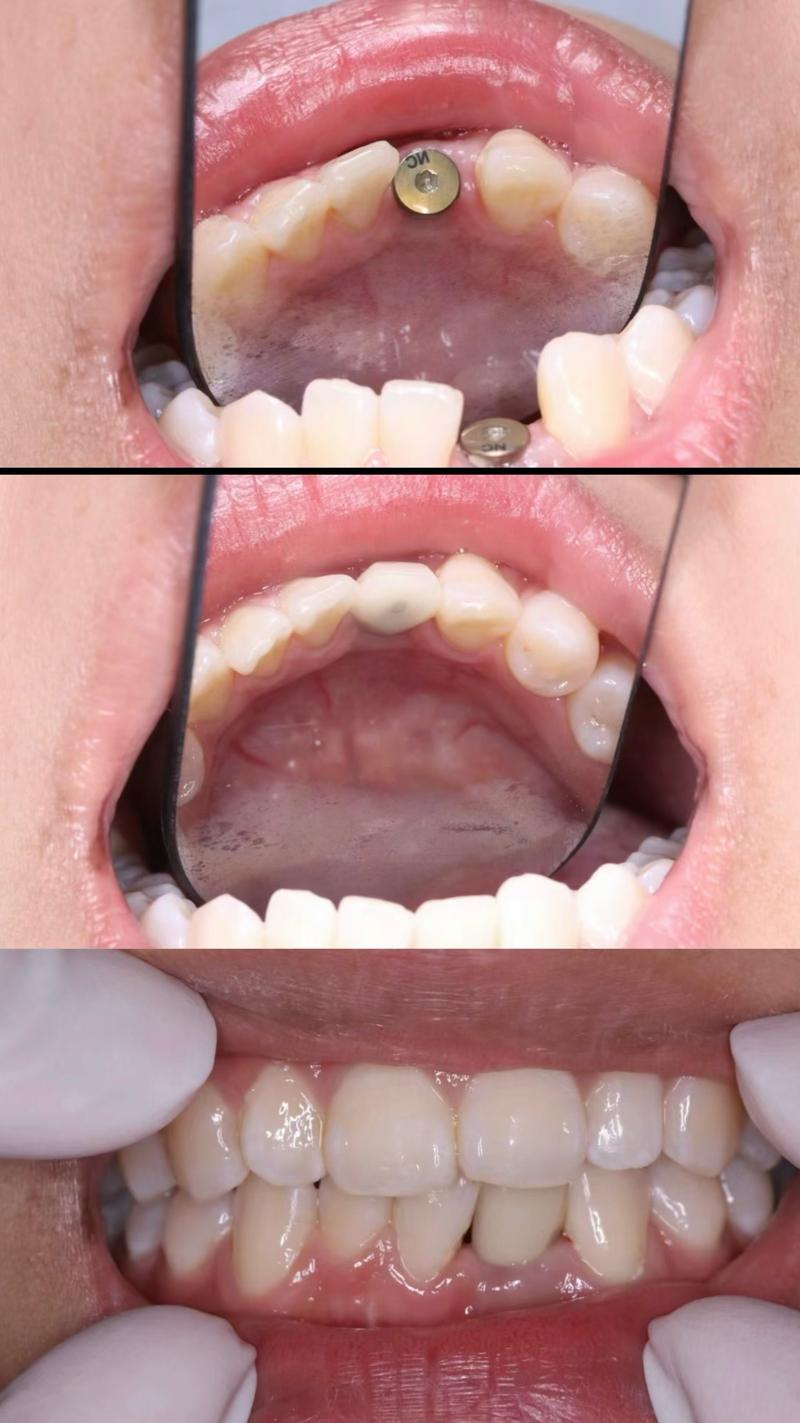

传统种植牙需切开牙龈、翻瓣暴露骨面,手术创伤较大,术后肿胀疼痛明显,恢复期常需1-2周,而微创种牙依托数字化技术与精密设备,实现了“不翻瓣”或“小切口”种植,核心优势在于精准、微创、高效,具体而言,术前通过CBCT、口扫仪获取口腔三维数据,结合计算机辅助设计(CAD)与3D打印技术,制作个性化种植导板,术中导板能精准定位种植体的位置、角度和深度,避免损伤神经、血管等重要组织,手术过程仅需局部麻醉,切口通常小于4mm,无需缝合或仅需1-2针,术后肿胀轻微,多数患者当天即可进食软食,3-5天恢复正常生活。

值得注意的是,南京微创种牙已实现“全流程数字化”:从术前的口腔数据采集、方案设计,到术中的导板导航、种植体植入,再到术后的牙冠设计与佩戴,每个环节均依托精准数据,将误差控制在0.1mm以内,对于半口缺牙患者,All-on-4微创种植技术仅需植入4颗种植体即可支撑半口牙桥,避免全口植骨,手术时间缩短至1-2小时,当天戴牙恢复咀嚼功能,大幅提升患者生活质量。